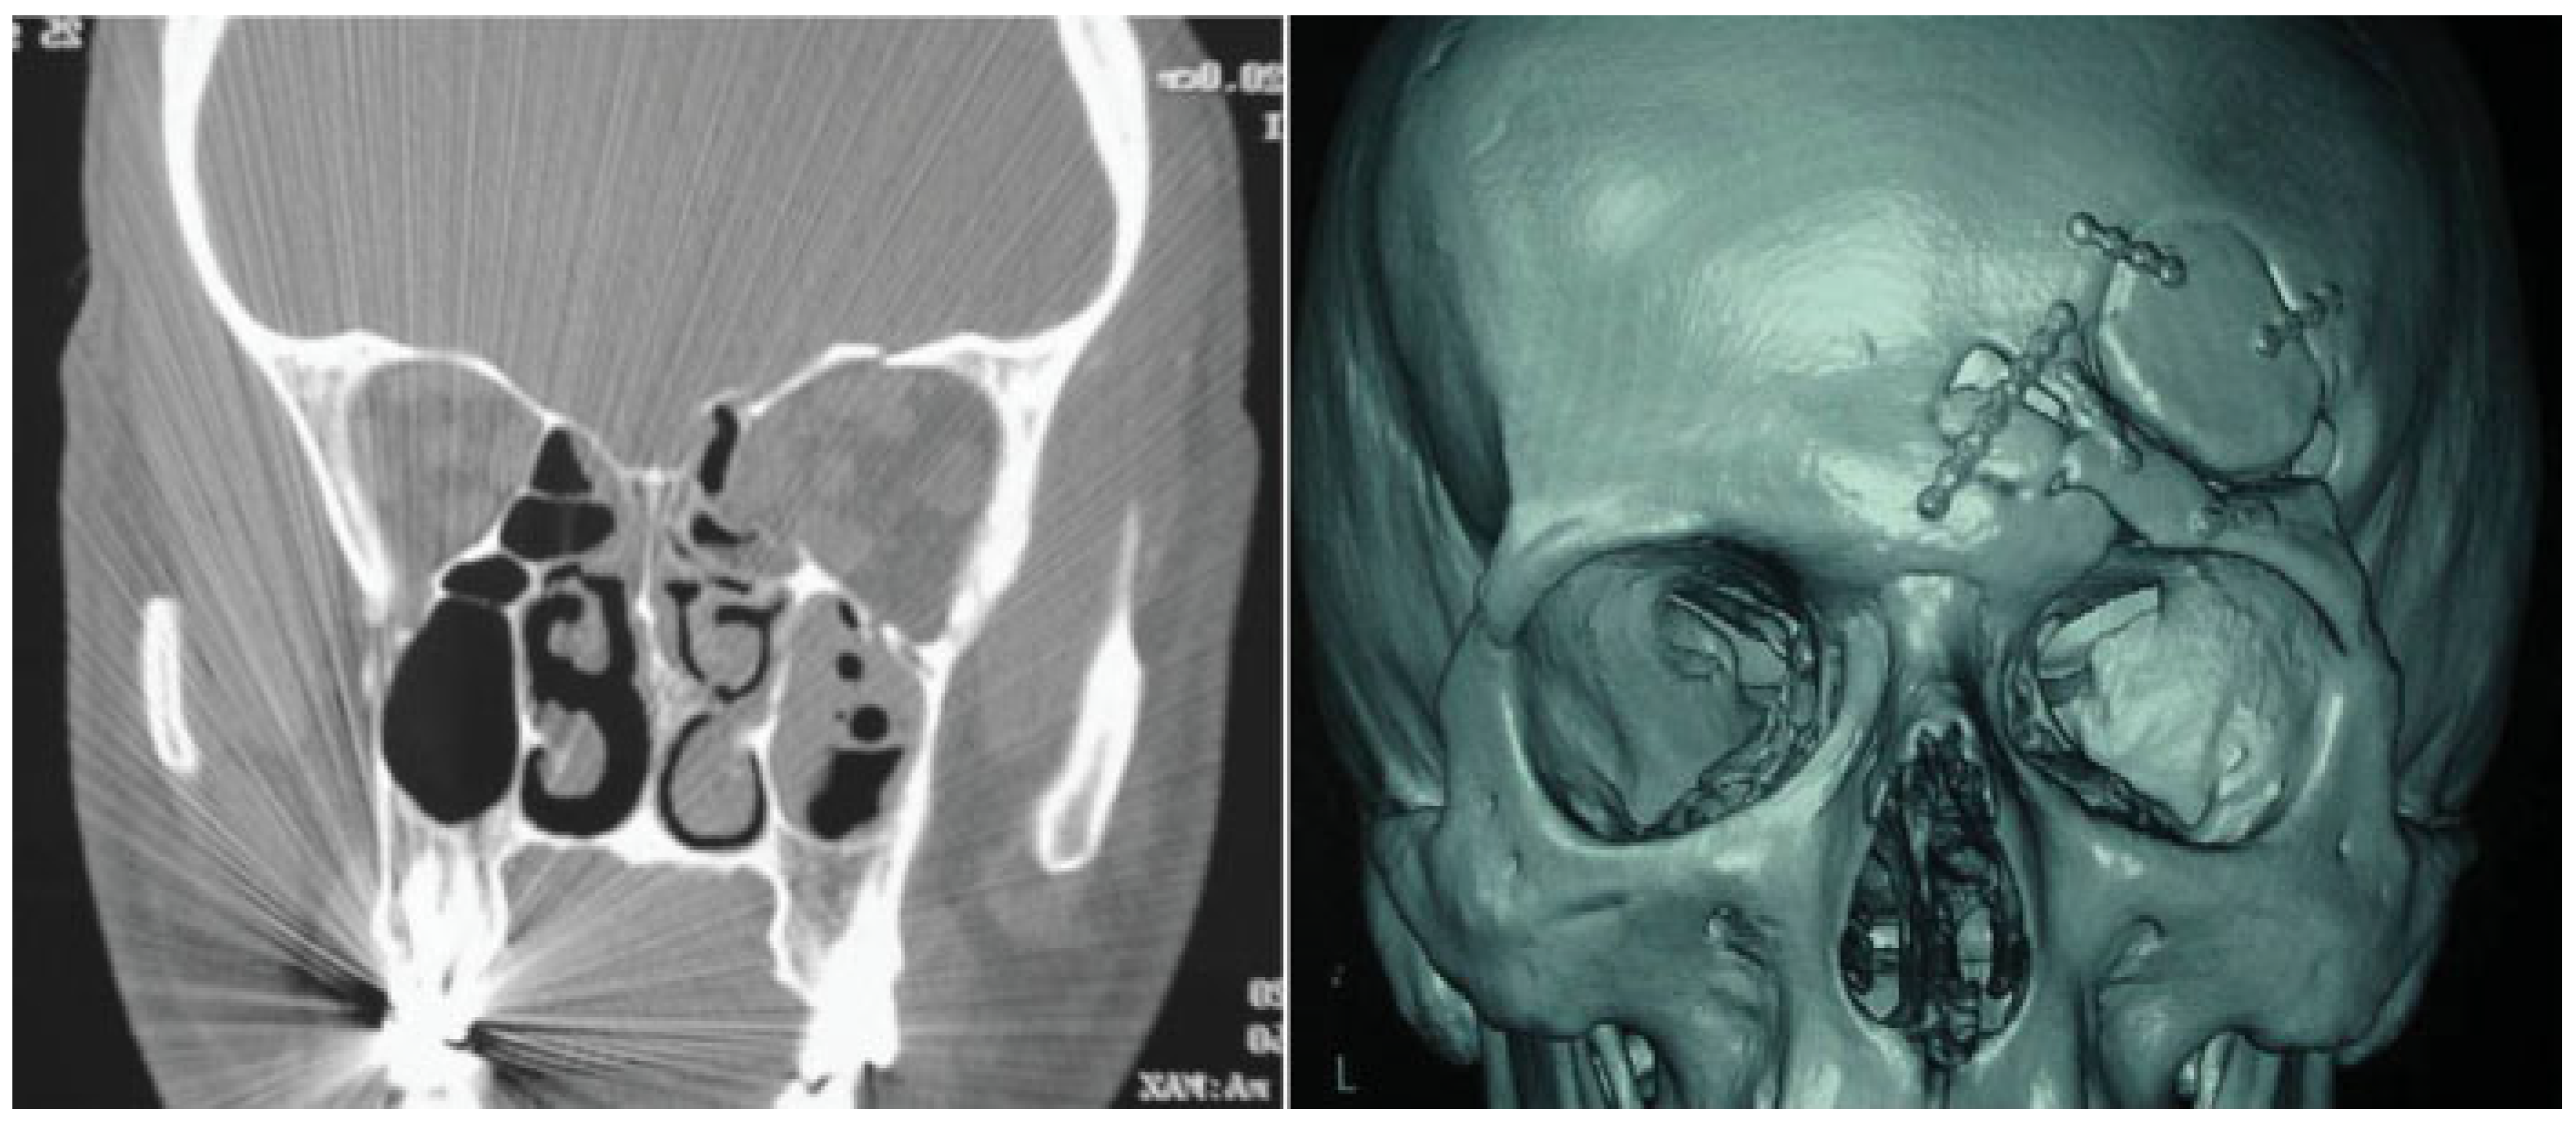

A 22-year-old man was referred to our department for a craniofacial trauma caused by a sport accident. The patient presented a visible and palpable frontal bone depression, periorbital ecchymosis, and eyelid ptosis (Figure 1). A computed tomography (CT) scan showed displaced frontal sinus anterior table fracture associated with orbital roof fracture with intact nasofrontal drainage system (Figure 2). The fractures were treated through a unilateral zigzag pretrichial incision exposing a wide surgical field allowing open reduction and internal rigid fixation (Figure 3). A postoperative CT scan showed a good restored bone contour (Figure 4). Surgical incision healed without complications (Figure 5), and after 20 months of follow-up, scar is quasi invisible (Figure 6).

Figure 2. Preoperative coronal and axial computed tomography images.